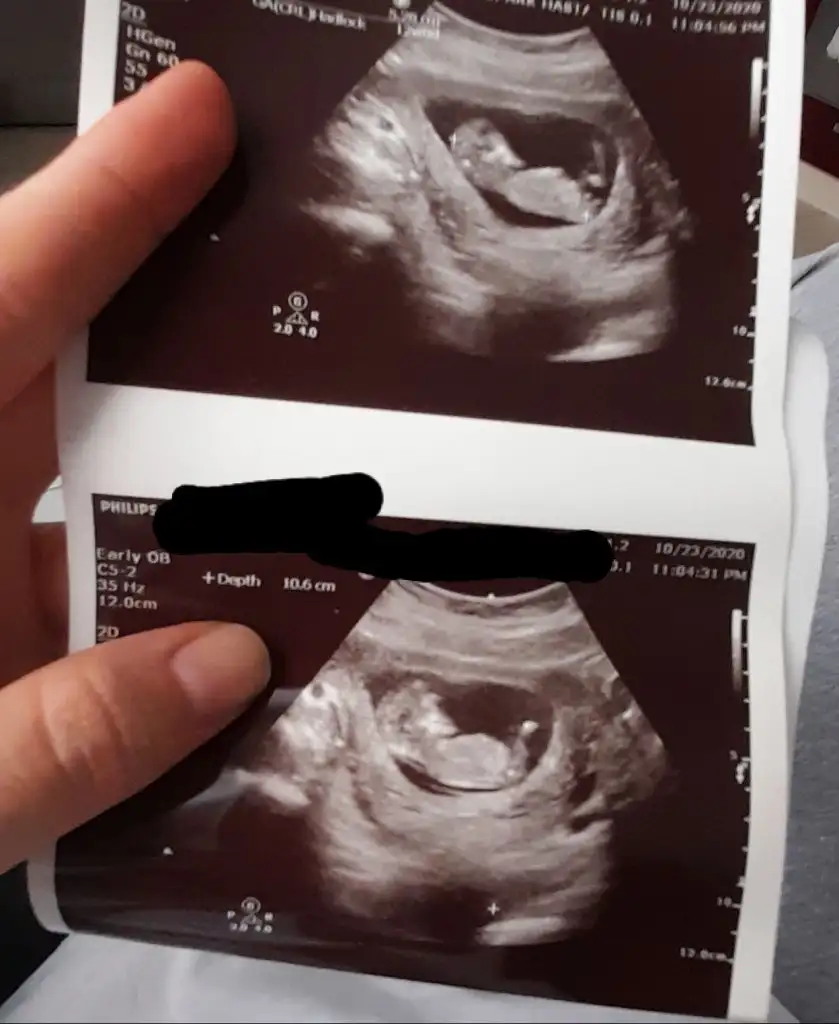

banada tahmin yapabilir misiniz 12haftalik![]()

Bence senin bebiş kız canım bende az cok anlıyorum tahminlerim de cogu zaman tutuyor